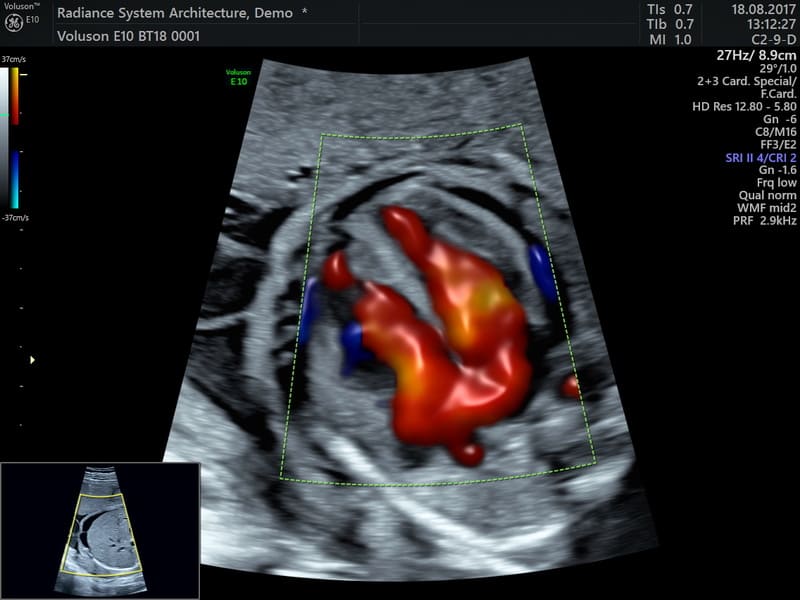

HDlive™ Flow e HDlive™ Flow Silhouette: Applica tutte le caratteristiche presenti in HDlive™ e HDlive™ Silhouette al rendering con campionamento di flusso volumetrico Color Doppler, Power e HDFlow™.